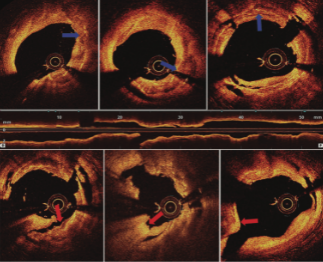

This case highlights that rotational atherectomy is merely paving the road and may help in superficial calcifications. It also showed the useful role of optical coherence tomography (OCT) for guiding the appropriate treatment strategy....

To our knowledge, this is the first OCT description of this complication.